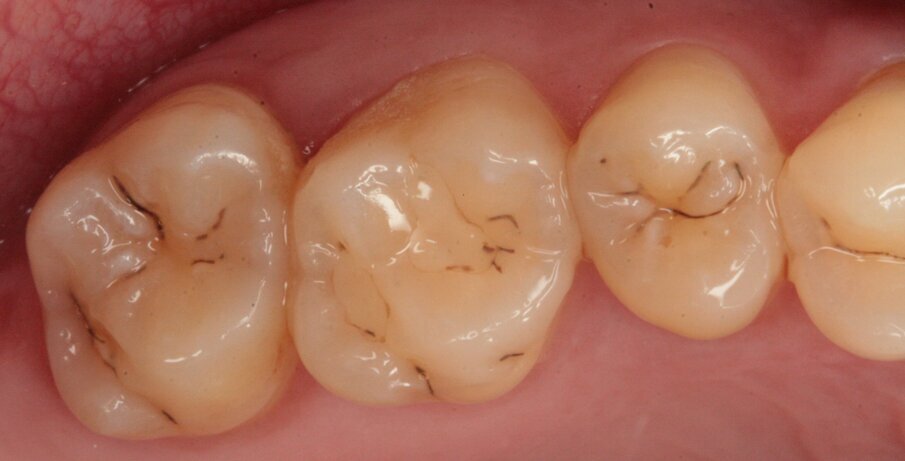

Fig.1_Visione occlusale dell’arcata superiore.

Fig. 5_Visione occlusale di 16 e 17.